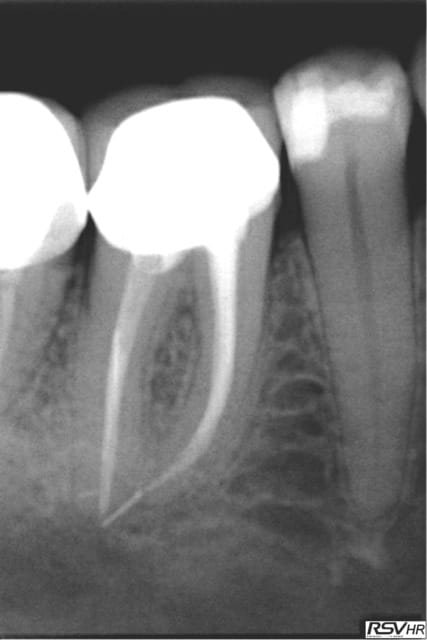

Autrement j'ai joint 2 radios en 2011 ou suite à une bio sous digue+ hypo à 2,5% j'ai cassé 2 Niti un ,racine mésiale de 46

et en distal dans sans doute un canal secondaire.Tout cela baignait dans l'hypo.Je n'étais pas fière( surement pas assez de cathétérisme apex mésial dépassé etc...)Et donc j'ai fait un suivi

et en 2013 le périapex semble guéri,pas de sensibilité à la pression, la nature est sympa et bien sur je ne casse plus de Niti

dans mes endos.....

2011 yf6dsf - Eugenol

2013 dibdsa - Eugenol